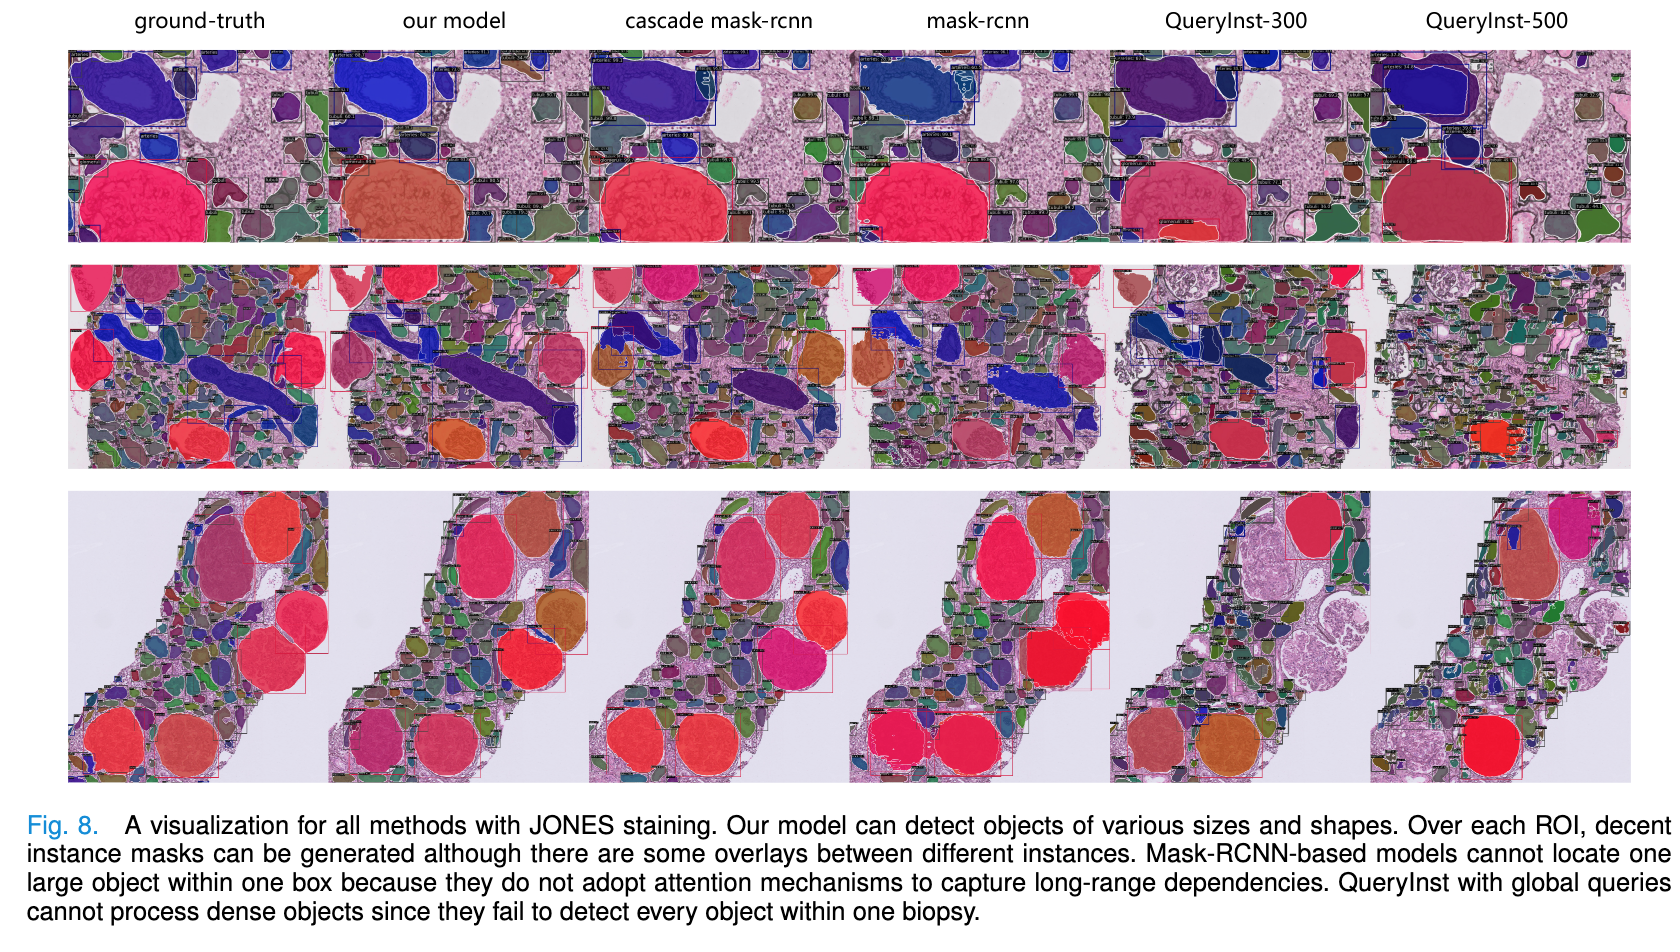

| Advances in Kidney Biopsy Structural Assessment through Dense Instance Segmentation Authors Zhan Xiong, Junling He, Pieter Valkema, Tri Q. Nguyen, Maarten Naesens, Jesper Kers, Fons J. Verbeek 肾活检是诊断肾脏疾病的金标准。肾脏病理学家专家做出的病变评分是半定量的,并且观察者之间的变异性很高。因此,自动获取每个分割的解剖对象的统计数据可以在减少劳动力和观察者之间的变异性方面带来显着的好处。然而,活检的实例分割一直是一个具有挑战性的问题,因为a平均有大约300到1000个密集接触的解剖结构,b具有至少3个的多个类,c具有不同的尺寸和形状。当前使用的实例分割模型无法以有效且通用的方式同时应对这些挑战。在本文中,我们提出了第一个无锚实例分割模型,该模型结合了扩散模型、变压器模块和 RCNN 区域卷积神经网络。我们的模型仅在一台 NVIDIA GeForce RTX 3090 GPU 上进行训练,但可以有效识别肾活检中 3 种常见解剖对象类别(即肾小球、肾小管和动脉)的 500 多个对象。我们的数据集由从 148 张琼斯银染肾全切片图像 WSI 中提取的 303 个斑块组成,其中 249 个斑块用于训练,54 个斑块用于评估。此外,无需调整或重新训练,该模型可以直接转移其域,从 PAS 染色的 WSI 中生成良好的实例分割结果。 |